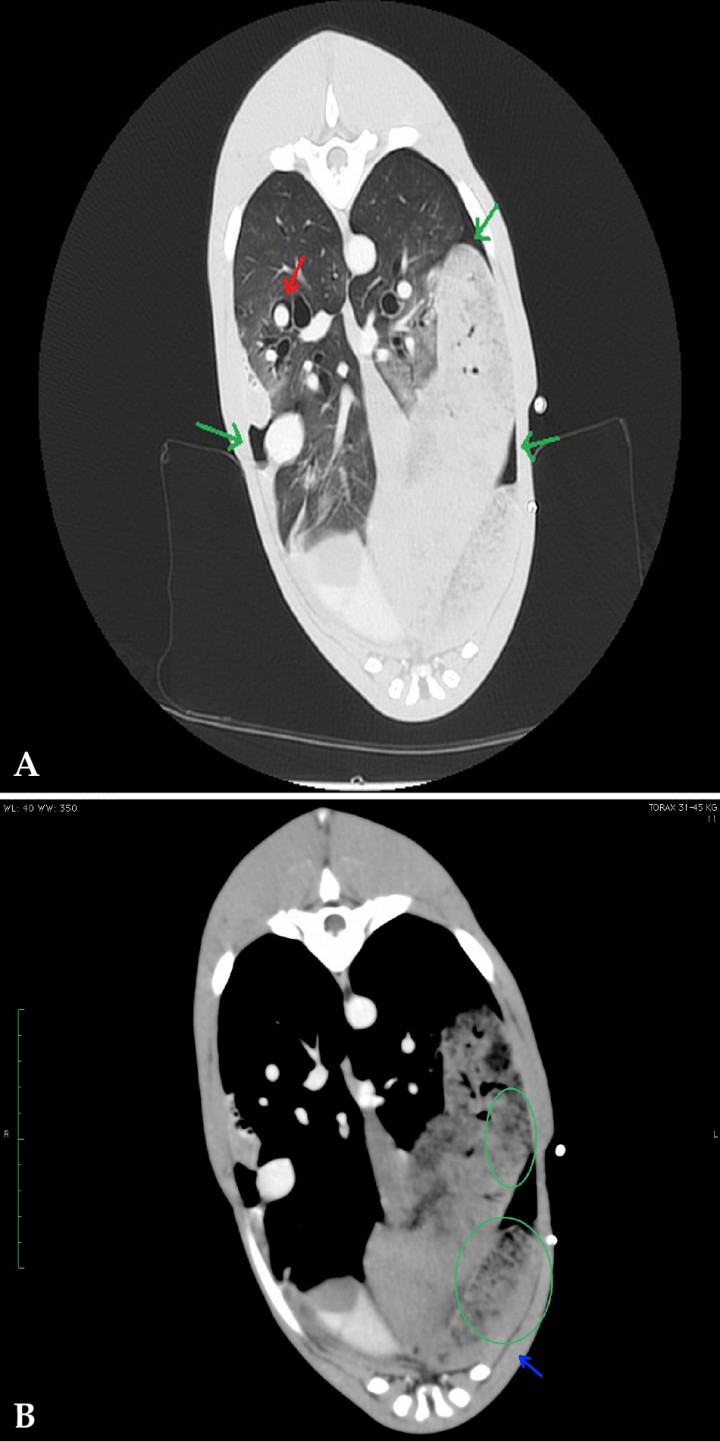

En el interior de la porción caudal del lóbulo craneal izquierdo se observó un patrón vesicular. Se evidenció un pequeño volumen de neumotórax, más acusado en hemitórax izquierdo, coincidiendo con la posición del drenaje pleural, así como un discreto neumomediastino y enfisema intersticial alrededor de la arteria pulmonar del lóbulo caudal derecho (Fig. 5).

<p>(<strong>A</strong>) Corte transversal en ventana pulmón. (<strong>B</strong>) Corte transversal en ventana tejido blando. Lóbulo pulmonar torsionado (flecha azul) con patrón vesicular visible en la porción caudal del lóbulo craneal izquierdo (círculo verde). Pequeño volumen de aire en espacio pleural (flechas verdes) y de enfisema intersticial alrededor de la arteria pulmonar del lóbulo caudal derecho (flecha roja).</p>

(A) Corte transversal en ventana pulmón. (B) Corte transversal en ventana tejido blando. Lóbulo pulmonar torsionado (flecha azul) con patrón vesicular visible en la porción caudal del lóbulo craneal izquierdo (círculo verde). Pequeño volumen de aire en espacio pleural (flechas verdes) y de enfisema intersticial alrededor de la arteria pulmonar del lóbulo caudal derecho (flecha roja).